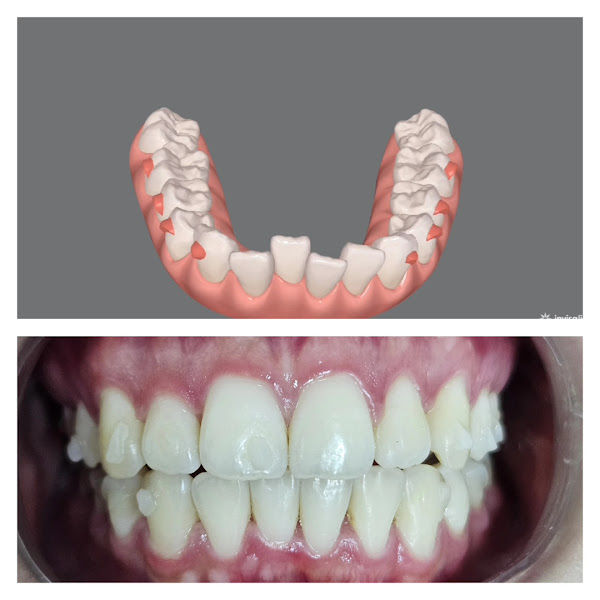

Fotos